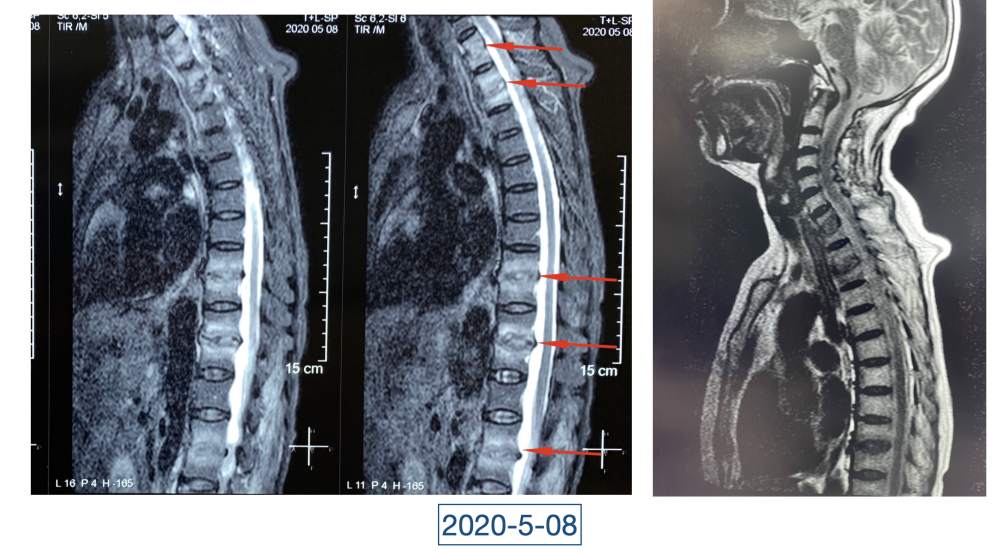

经过科室讨论、会诊,李辉也查阅了很多资料,按照黄大娘的症状,他跟之前的接诊医生一样,觉得应该是骨关节感染。可之前的穿刺、培养各种检查也做过,为什么没有找到致病菌?李辉想,或许是检查中出现了问题,没有查对地方。于是他决定,在B超引导下骨穿刺,通过最新技术精准定位病灶,只有这样也许才能抓到真正的“罪犯”。

在黄大娘入院第四天,李辉将她推入检查室,结果很快出来了,为烟曲霉菌感染。这个结果验证了李辉的想法,也解释了此前抗感染药物为何一直不奏效。“找到元凶就好办了,对症用药就可以。真菌感染本来治疗时间就很长,骨科类感染灶治疗时间更长,用了5个月的时间,终于治好了。”

近日随访得知黄大娘身体好转,李辉脸上的笑容掩饰不住,他说,据查阅文献,11处感染灶,这是全世界感染灶最多的骨关节感染,但现在,这罕见、复杂的病已经被治愈。